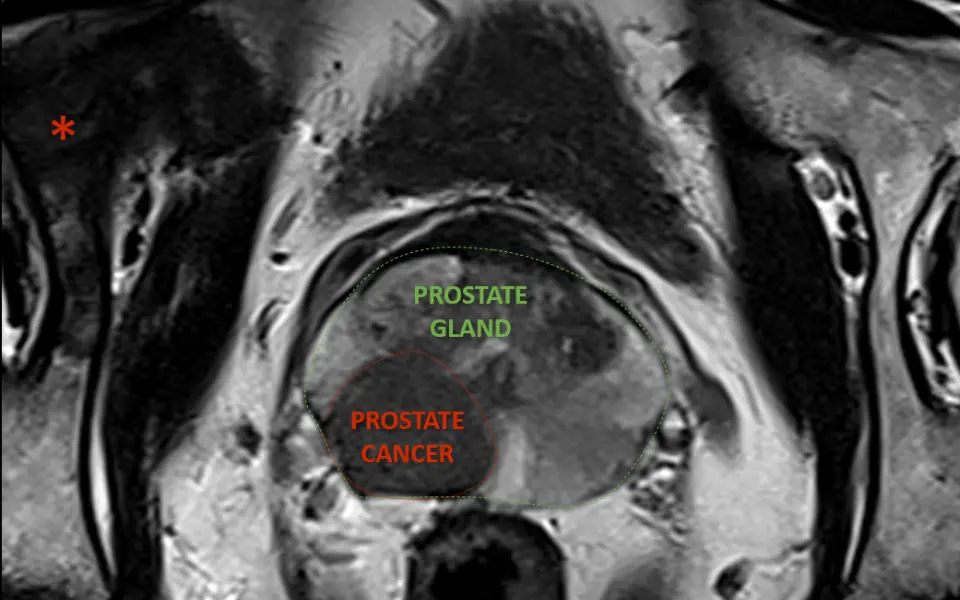

Magnetic Resonance Imaging (MRI) is utilised to measure the size of the prostate and to detect any areas of abnormality within the gland itself and surrounding areas of the pelvis. The MRI scan can also be used to guide MRI-Ultrasound fusion biopsy.

For this examination, your pelvis is positioned in the middle of the MRI machine, allowing your head to be at one end of the machine. You are given an injection of contrast to further assist in tissue characterisation.  The examination typically takes 30 minutes. Read more about MRI prostate cancer imaging services as part of Prostate Cancer awareness.